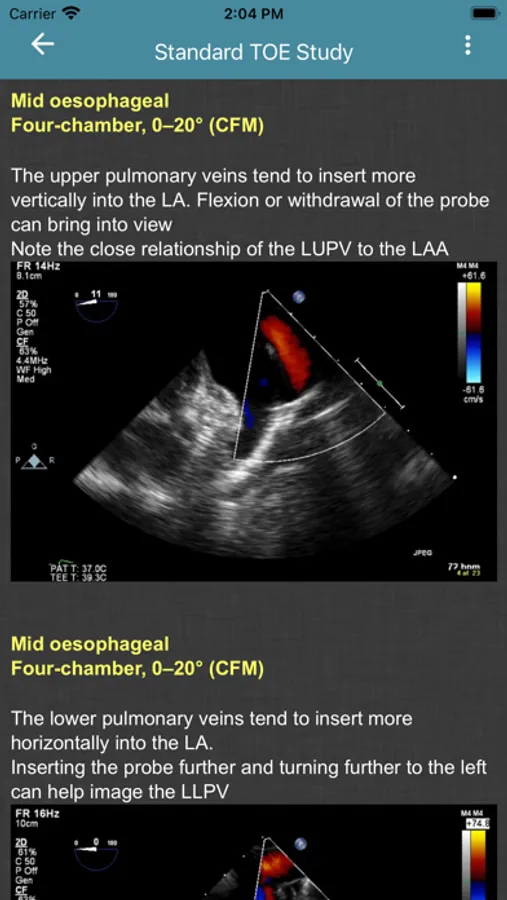

- Standard TOE Study

Screenshot 1Screenshot 2Screenshot 3Screenshot 4Screenshot 5Screenshot 6Screenshot 7Screenshot 8Screenshot 9Screenshot 10